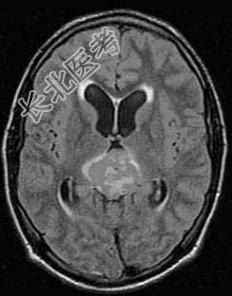

- 单项选择题松果体区肿瘤(如图所示)的临床表现哪项错误 ( )

A、上视障碍

B、瞳孔对光反应和调节反应障碍

C、尿崩症

D、颅内压降低

E、水平眼球震颤